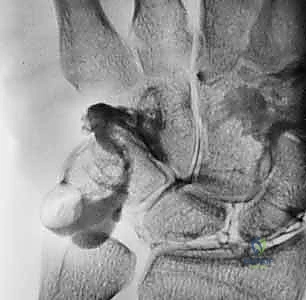

- Fluoroscopic Confirmation: Use intraoperative fluoroscopy to confirm anatomical reduction and optimal K-wire placement. Check both AP and lateral views. Ensure the wires are not impinging on articular surfaces or neurovascular structures.

- K-Wire Placement: Once reduced, we need to temporarily stabilize the joint.

- First K-wire: Insert a 0.045-inch or 0.062-inch smooth K-wire into the triquetrum at approximately a 45-degree angle, aiming towards the lunate. Advance this wire across the lunotriquetral joint and into the lunate. Ensure good purchase in both bones.

- Second K-wire: Place a second K-wire across the lunotriquetral joint, ideally starting from the lunate and crossing into the triquetrum, or vice-versa, to provide rotational stability. This creates a more rigid construct.